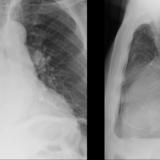

Aortic aneurysm

Date: 03/02/2014

Views: 2272